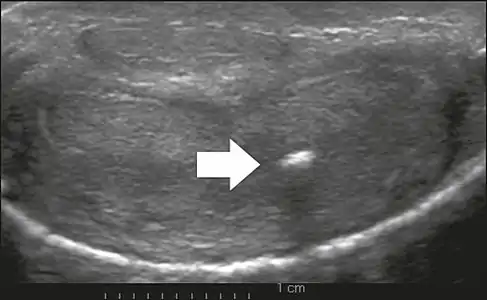

Transverse ultrasound of the penis, in a ventral view, in the middle portion of the penis. Note the echoic image with posterior acoustic shadowing, corresponding to calcification (arrow), in the left corpus cavernosum.[13]

On penile ultrasonography, the typical appearance is hyperechoic focal thickening of the tunica albuginea. Due to associated calcifications, the imaging of patients with Peyronie's disease shows acoustic shadowing, as illustrated in figures below. Less common findings, attributed to earlier stages of the disease (still mild fibrosis), are hypoechoic lesions with focal thickening of the paracavernous tissues, echoic focal thickening of the tunica without posterior acoustic shadowing, retractile isoechoic lesions with posterior attenuation of the beam, and focal loss of the continuity of the tunica albuginea. In the Doppler study, increased flow around the plaques can suggest inflammatory activity and the absence of flow can suggest disease stability. Ultrasound is useful for the identification of lesions and to determine their relationship with the neurovascular bundle. Individuals with Peyronie's disease can present with erectile dysfunction, often related to venous leakage, due to insufficient drainage at the site of the plaque. Although plaques are more common on the dorsum of the penis, they can also be seen on the ventral face, lateral face, or septum.[13]